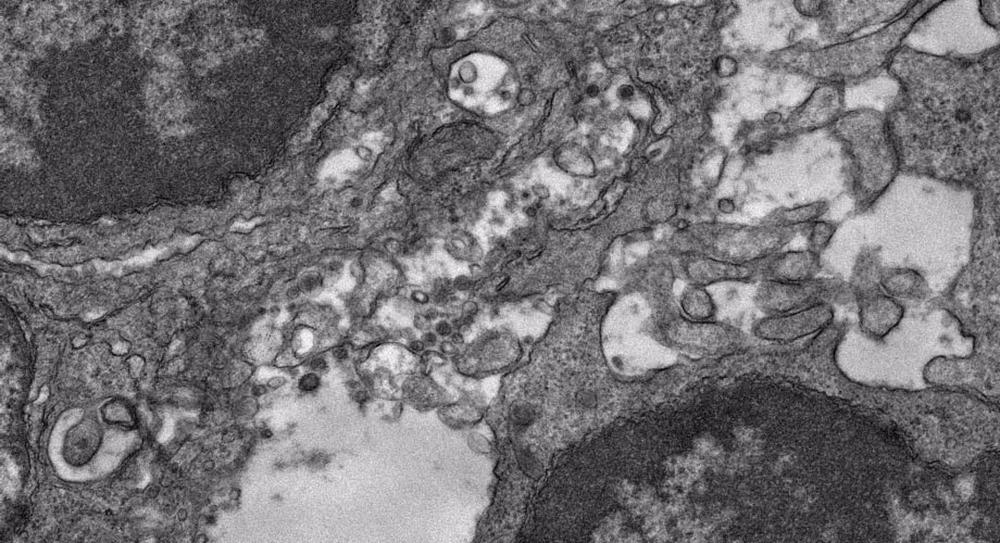

«Tradicionalmente, los médicos han irradiado todos los ganglios linfáticos que rodean a un tumor en un proceso denominado ‘irradiación ganglionar electiva’. Pero el problema de este planteamiento de ‘tierra quemada’ en la era de la inmunoterapia es que al hacerlo también se elimina la fuente de células inmunitarias sobre las que actúa la inmunoterapia. Los ganglios linfáticos son el centro de preparación y expansión de las principales células inmunitarias que pueden ir a luchar contra el cáncer», ha explicado la doctora Sana Karam, autora principal del estudio, que se ha publicado en la revista científica ‘Nature Communications’.

Karam y su equipo descubrieron que la irradiación de todos los ganglios linfáticos alrededor de un tumor disminuía significativamente la memoria inmunitaria y la propagación de antígenos, lo que creaba un riesgo mucho mayor de que el cáncer se extendiera en partes del cuerpo alejadas del lugar original del tumor. «Fue un hallazgo inesperado», dice Karam.